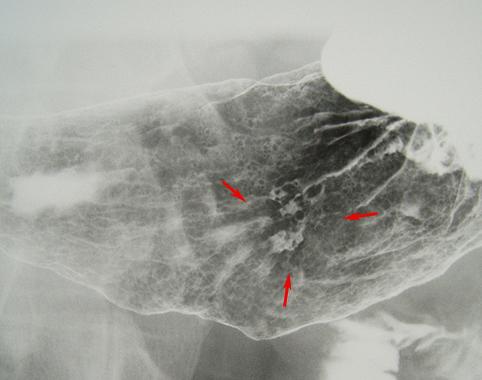

疾病(病理主体)的分类恶性上皮性肿瘤/印戒细胞癌

部位(按器官分)胃(部位)/胃角

检查方法X线

肿瘤的肉眼分类0型(表在型)/IIc型(IIc+III)

肿瘤最大直径20~24

肿瘤的深度m